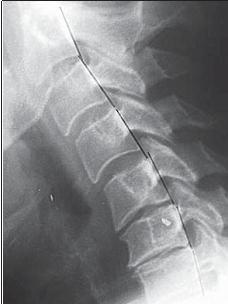

Дезинтеграция патологически изменённого пульпозного ядра неминуемо изменяет его объём. При этом закономерно усиливается компрессия фиброзного кольца и в той или иной степени нарушается расположение структур сегмента позвоночника. Активация процессов микрорубцевания после периодов интенсивной деструкции и постепенное накопление в тканях межпозвонкового диска склеротических изменений (кстати, склерозом называют замену паренхимы органов плотной соединительной тканью) приводит к нарушению подвижности, а также нарушению распределения нагрузок в дугоотросчатых суставах. Это в свою очередь вызывает прогрессирующие нарушения трофики межпозвонкового диска и со временем завершается коллагенизацией ткани — «хрящевой метаплазией» с замещением зоны пульпозного ядра волокнистым хрящом. Метаплазия (от греч. metaplasis — преобразование) — это превращение одной разновидности ткани в другую, отличную от первой морфологически и функционально при сохранении её основной видовой принадлежности. При таких патологических процессах фиброзное кольцо растрескивается более интенсивно именно в зонах «хрящевой метаплазии», что в дальнейшем приводит к развитию протрузий или грыж межпозвонковых дисков. Вторичность поражения фиброзного кольца подтверждается тем, что трещины распределяются на кольцо изнутри межпозвонкового диска и степень их распространения пропорциональна выраженности деструкции пульпозного ядра. При сегментарной нестабильности происходят движения в виде чрезмерного сгибания и разгибания, а также несвойственные скольжения позвонков кпереди или кзади. При функциональной рентгенографии это определяется как смещение тела вышележащего позвонка при сгибании несколько кпереди (рентгенограмма № 2), а при разгибании — кзади (рентгенограмма № 3), или изменение равномерной дуги (лордоза) с локальным выпрямлением (или усугублением). МРТ № 8

Рентгенограмма № 2

Рентгенограмма № 3 Сегментарная нестабильность клинически может проявляться периодическим болевым синдромом при неловком повороте туловища, чрезмерном его сгибании, разгибании или длительном статическом положении, при подъёме, после длительного нахождения тела в положении сидя (так называемые «стартовые боли», когда тяжелее всего даются первые шаги). Но хочу обратить ваше внимание на то, что болевой синдром как раз является уникальным «охранным», защитным механизмом организма, во избежание той тотальной перегрузки поражённого диска, о которой мы говорили выше, а также катастрофических «микроземлетрясений» в данном сегменте. В этом случае организм оперативно реагирует на болевую реакцию мышечным спазмом или, как часто говорят мануальные терапевты, «мышечным блоком», за счёт дефанса (напряжения) коротких мышц позвоночника. В свою очередь это иммобилизирует (от лат. immobilis — неподвижный) на какое-то время поражённый сегмент или сегменты позвоночника для того, чтобы дать им возможность плавно переключиться с одного состояния работы на другое, тем самым защитить от дополнительной травматизации. Ведь в отличие от здоровых дисков дегенерирующие диски включаются в работу не так быстро, вследствие частичной утраты своих функциональных возможностей. Как говорится, природа до последнего борется за поражённый сегмент, пытаясь всеми способами сдержать дальнейшее развитие нестабильности и прогрессирование дегенерации диска. А если ей в этот период ещё и помочь, к примеру заняться плаванием (без нагрузок — пляжный вариант), ходьбой пешком до десяти километров в день (лечебный терренкур — имеется в виду метод лечения дозированной во времени и расстоянии ходьбой, а не тренажёр-дорожка для ходьбы) и т. д., то подобные мышечные спазмы вскоре пройдут и процесс быстрого развития дегенерации диска значительно затормозится. В общем, жизнь в гармонии и взаимопонимании со своим организмом никому не помешает, тем более, что на кону стоит ваше здоровье, а следовательно, ваша повседневная бытовая деятельность, работа, взаимоотношения с окружающими. К сожалению, многие «специалисты» в области вертебрологии расценивают данную ситуацию как «патологию, при которой мышечный блок обязательно необходимо разблокировать». Не вникая в суть происходящих в организме процессов, они необоснованно применяют для «лечения» пациента мануальную терапию, различные методы вытяжения (растяжения) позвоночника, рекомендуют больному заниматься фитнесом, бегом и другими интенсивными физическими нагрузками. Однако всё это не только не останавливает развитие нестабильности в позвоночно-двигательном сегменте, но и способствует более быстрому (реактивному) дальнейшему прогрессированию дегенерации межпозвонкового диска. Если бы о данном отрицательном эффекте не было известно в научном мире, это было бы ещё полбеды. Так ведь дегенеративные поражения позвоночно-двигательных сегментов, как и позвоночника в целом, изучаются уже почти столетие. Сорок лет назад (в 1970!) об этой проблеме писал ещё заведующий кафедрой ортопедии и травматологии Новосибирского государственного медицинского института Я. Л. Цивьян: «Если назначить при сегментарной нестабильности тракционные методы лечения, мануальную терапию, интенсивные занятия спортом, то данные методы будут только способствовать «расшатыванию» позвоночного сегмента, стимулируя прогрессирование дегенеративно-дистрофического процесса в межпозвонковом диске, и не принесут больному пользу, а скорее вред». Что может скрываться за болями в спине? Следует помнить, что медицина, хоть и является наукой приблизительной, вернее не совсем точной (это действительно так) и не гарантирующей стопроцентный положительный исход лечения в любом конкретном случае (и это, к сожалению, тоже правда), но значительно снизить риски вполне способна. Если боли в позвоночнике вынудили вас обратиться к врачу по месту жительства, то я бы посоветовал вам обратить внимание на следующие моменты в действиях данного специалиста: — на приёме врач, выслушав ваши жалобы, произведя внешний осмотр, ставит вам окончательный диагноз без дополнительного обследования (магнитнорезонансной томографии (МРТ) или хотя бы компьютерной томографии (КТ)); — врач назначает в качестве лечения (при неустановленном точном диагнозе (!), в отсутствии результатов обследования) вытяжения, висы на перекладине, ЛФК и другие методы, направленные на физическое или механическое воздействие на сегменты позвоночника или на позвоночник в целом; исключение составляют медикаментозные препараты, которые он обязан назначить как первую помощь до получения результатов объективного обследования и уточнения диагноза; |